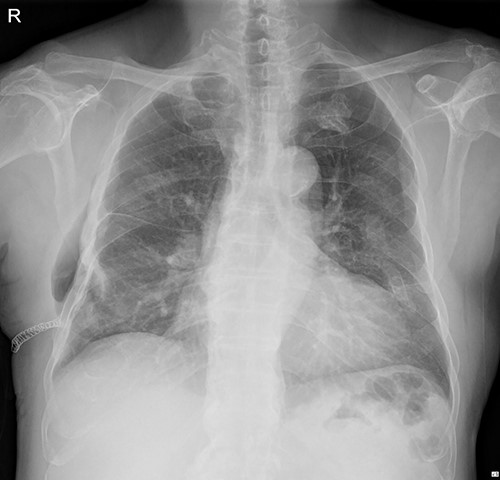

The patient visited the outpatient clinic on 07 March 2022, for stitches removal, complaining of mild discomfort on the operation site (Fig. 3.). Chest X-ray showed a large, localized submuscular emphysema between the rib cage and the SAM. The surgical wound was clear. Stitches were removed as planned, and the patient was asked to revisit the outpatient clinic 3 days later.